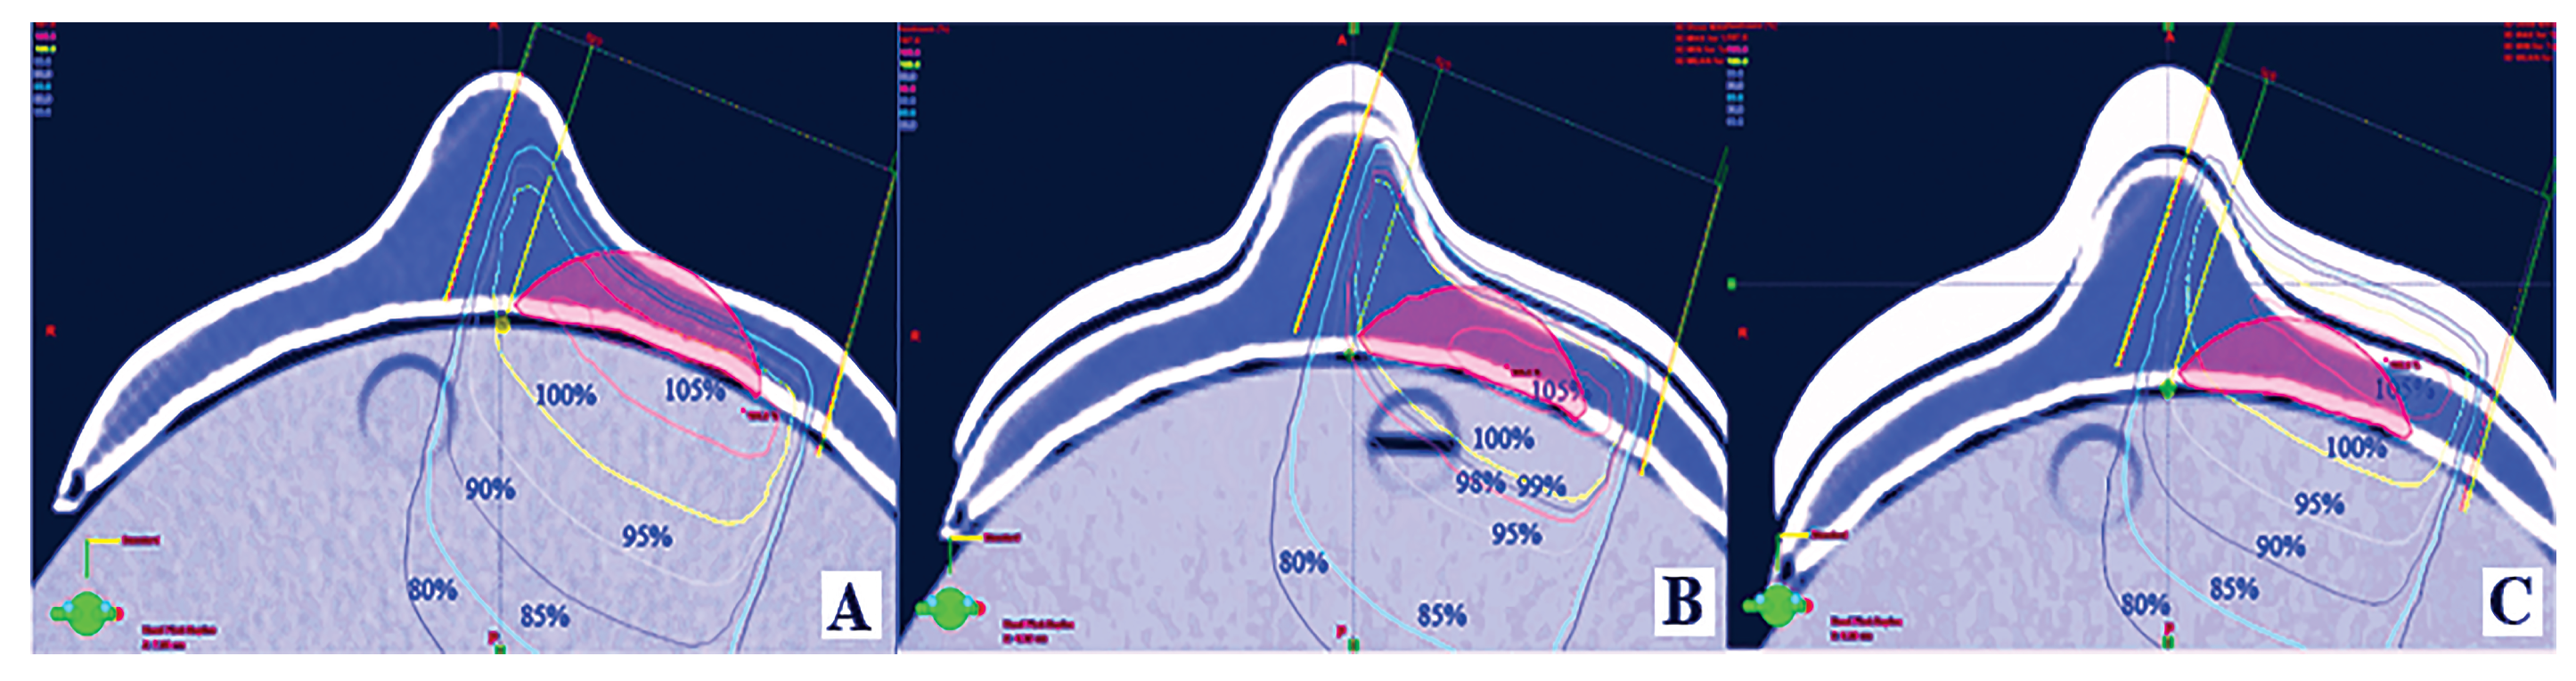

2.4. Dosimetric Evaluation

3.3. In Vitro Dose Verification Using 3D-Printed Devices